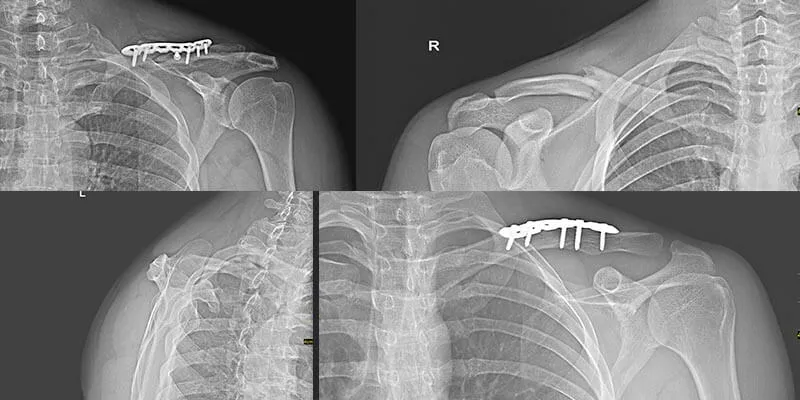

Rehabilitacja po złamaniu obojczyka to proces, który może trwać różnie w zależności od wielu czynników. Czas rehabilitacji po złamaniu obojczyka jest uzależniony głównie od rodzaju złamania oraz stanu zdrowia pacjenta. W przypadku prostych złamań, które nie wymagają interwencji chirurgicznej, rehabilitacja zazwyczaj trwa od 3 do 6 miesięcy. Natomiast w sytuacjach, gdy złamanie jest z przemieszczeniem i konieczna jest operacja, czas ten może wydłużyć się do 12 miesięcy.

Czas rehabilitacji różni się w zależności od tego, czy złamanie jest proste, czy złożone. Proste złamania bez przemieszczenia wymagają zazwyczaj krótszej rehabilitacji, trwającej od 3 do 6 miesięcy. W przypadku złamań z przemieszczeniem, które często wymagają operacji, rehabilitacja może trwać od 6 do 12 miesięcy, co wiąże się z bardziej skomplikowanym procesem zdrowienia.